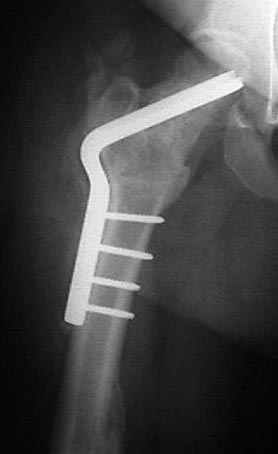

5:24 Рентгенограмма таза, вызывают врача ортопеда (снимок N1), его диагноз: закрытый переломо-вывих правого тазабедренного сустава, получает добро на закрытую репозицию в приемном отделении

N 2

На рисунке N1 предоперационный план лечения ложного сустава шейки бедра- линия ложного сустава, угол и направление введения импланта, клиновидная остеотомия в градусах и миллиметрах, второй снимок после коррекции, расчет, на сколько удлиняется конечность и размеры импланта;

N3 рисунок окончательный снимок, после операции моя рентгенограмма должен выглядеть примерно как эта картина. На N4 снимке клин перед удалением; N5 послеоперации 3 нед.; N6 окончательная рентгенограмма.

варус при проксимальном отделе 95 градусной пластиной.